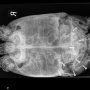

Poche risorse e chiamate deviate: è Sos picchetti veterinari

‘Nel Locarnese abbiamo un problema’: la battaglia con Ovt, Ufficio sanità e Veterinario cantonale del responsabile della pianificazione, Boris Pfänder

Nel Locarnese c’è un problema